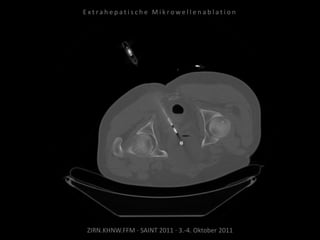

Metastase medial des linken

Musculus iliacus:

1 Nadelposition.